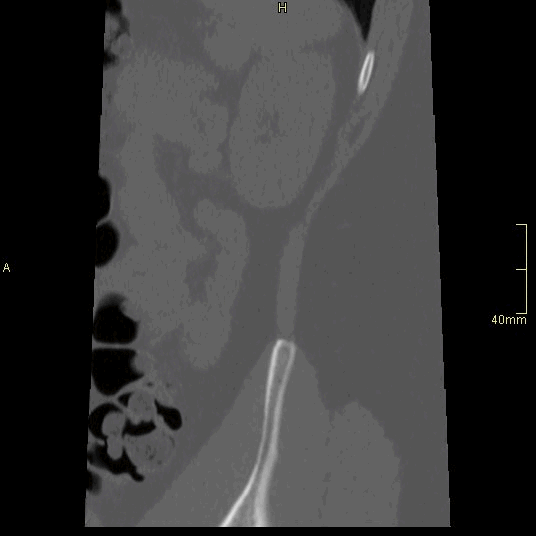

CT Lumbosacral Spine Non Contrast- Bone window (sagittal)